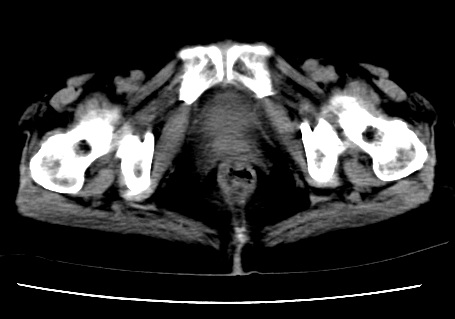

标题: CT23975:女61岁,腹部不适,明显消瘦 [打印本页]

标题: CT23975:女61岁,腹部不适,明显消瘦

既往5年前卵巢癌行子宫及附件切除,右乳癌术后一年,考虑腹膜转移?

大量腹水,考虑腹膜转移。肝脏低密度灶。1囊肿,2转移。

1)结合病史,考虑腹膜及网膜转移瘤。2)肝脏多发性低密度灶,不排除转移瘤。3)大量腹水。

考虑卵巢癌行子宫术后复发,并肝、腹腔 、大网膜转移可能性大。

大量腹水。